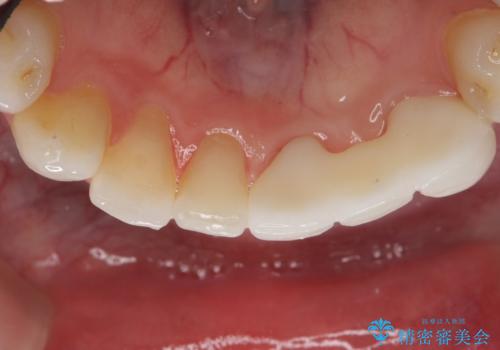

- 他院にて矯正治療を行ったが、左下の前歯の見た目が気になるのでセラミックで治したいといらっしゃった方の症例です。

左下123番のブリッジになるが、左下1番と3番の歯軸が合っておらず神経治療が必要になる可能性があるため部分矯正を提案したところ、希望されなかったため、そのままの歯軸でオールセラミッククラウンによる補綴を行いました。

今回用いたオールセラミッククラウンはジルコニアフレームという白い素材の上にセラミックを盛っているため、審美性が非常に高いのが特徴です。

また、ジルコニアは人工ダイヤモンドの材料にも使われているほど高い強度を持っており、そのためオールセラミッククラウンは審美性だけでなく、奥歯やブリッジの補綴も可能とするクラウンです。